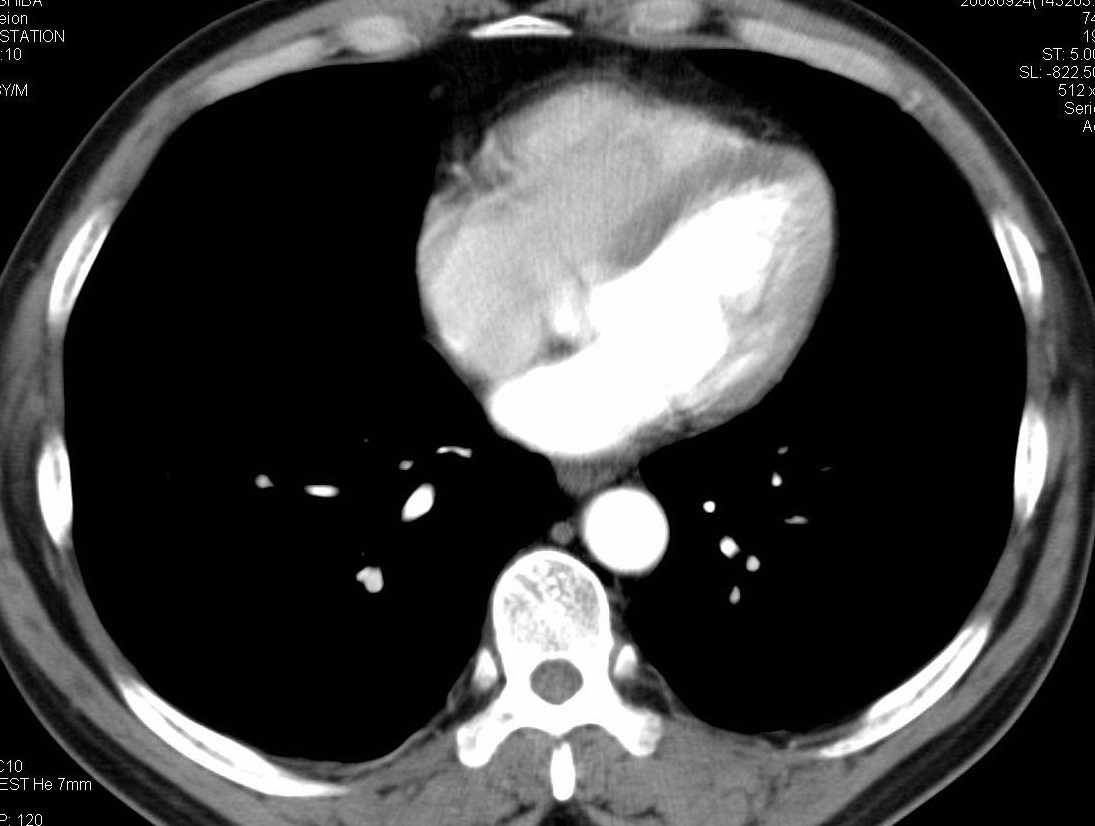

标题: CT15857:男性 58岁 咳痰带血 无发热 请各位大侠发表一下意见 [打印本页]

标题: CT15857:男性 58岁 咳痰带血 无发热 请各位大侠发表一下意见

两肺下叶肺纹理增多、增粗并呈“树芽状”改变。支气管扩张呈囊状,部分呈柱状改变。其周围可见散在的斑片样及条索样密度增高影,右肺下叶近叶间胸膜可见一形态不规则的高密度结节影,并与胸膜粘连。

考虑:支扩并发感染。

双肺多发炎性病灶,结核可能性大,建议抗炎治疗复查.右肺下叶前基底段结节灶,高度警惕肺癌可能

双肺间质性改变(间质纤维化?)伴支扩。右肺下叶有毛刺的小结节,考虑周围型肺癌可能性。